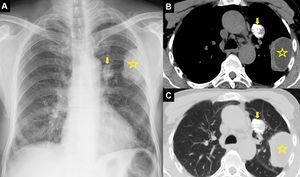

Posteroanterior (PA) chest radiograph (A) shows a perihilar calcified lesion (arrow) and a peripheral radiopaque lesion (star) with smooth margin in the left lung. Thoracic computed tomography mediastinal (B) and parenchymal window axial sections (C) show a 30mm×24mm lesion with diffuse calcification in the anterior segment of the upper lobe of the left lung (arrow) and a 60mm×40mm cystic lesion in the upper lobe apicoposterior segment (asterisk) in the pleural neighborhood.

A 67-year-old male presented with chest pain and cough. Thoracic computed tomography (CT) revealed two hydatid cysts in the left lung, one of which contained diffuse calcification (Fig. 1). There is a surgical indication for the other large hydatid cyst which is not calcified. The patient underwent a thoracotomy and the calcified cyst was excised at this stage both to confirm the diagnosis and for differential diagnosis. The other hydatid cyst underwent cystotomy and capitonage. Calcified hydatid cyst had no viable vesicles.